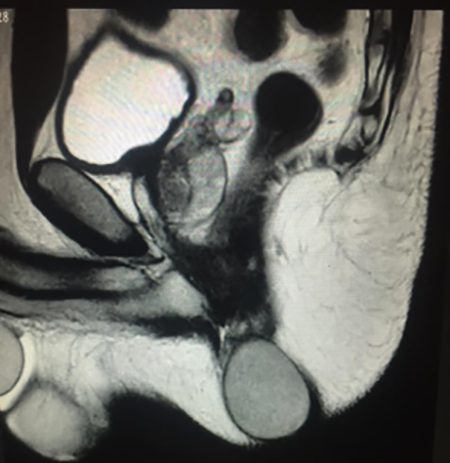

Paciente masculino de 45 años de edad que presenta tumoración perianal de 3 años de evolución. Dicha tumoración ha aumentado su tamaño en este periodo de tiempo y presenta incomodidad durante la higiene y prurito. No existe historia de cirugía o trauma del periné. Sus antecedentes personales revelan solo hipotiroidismo. El examen físico muestra una lesión situada en cuadrante anterolateral izquierdo, duroelástica, bordes netos, móvil, no adherida a planos profundos, no dolorosa a la palpación sin signos de complicación aguda (Figura 1). Estudio por imágenes, RMN: imagen nodular, redondeada, de bordes netos, señal homogénea, hiperintensa en T2 e intermedia en T1. Discretamente hiperintenso en difusión sin restricción significativa de ADC (Figura 2). Toma sutil contacto con MA del lado izquierdo, no involucra a los restantes componentes del canal anal. Mide 35 x 40 mm en plano axial y extensión cefalocaudal de 50 mm. Procedimiento quirúrgico: anestesia raquídea, posición de litotomía, anoscopia sin evidencia de afectación del canal anal, incisión losangica sobre lesión, disección hasta pared del quiste y ectomía del mismo. Cierre del lecho quirúrgico con técnica semicerrada. Alta sanatorial a las 24 h. Controles posquirúrgicos sin evidencia de recidiva.

Figura 2: Imagen nodular, redondeada, de bordes netos y señal homogénea. Mide 35 x 40 mm en plano axial y extensión cefalocaudal de 50 mm.